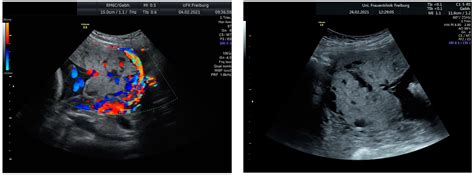

Modern obstetric imaging has made the identification of Placenta Accreta Spectrum much more reliable than in the past. Most cases are identified during the second or third-trimester ultrasound, where specific markers of abnormal placental vascularity are sought by trained sonographers.

Diagnostic Marker Description

Loss of Retroplacental Clear Zone The thin, hypoechoic area between the placenta and the uterus disappears.

Abnormal Placental Lacunae Large, irregular vascular spaces within the placenta that may resemble "Swiss cheese."

Bladder Wall Interruption The interface between the bladder and the uterus appears irregular, suggesting deep invasion.

Exophytic Mass Placental tissue bulging beyond the normal uterine contour.

⚠️ Note: While ultrasounds are highly effective, MRI is often utilized as an adjunct imaging tool to provide better visualization of the depth of invasion, especially in cases where the placenta is located on the posterior wall of the uterus.